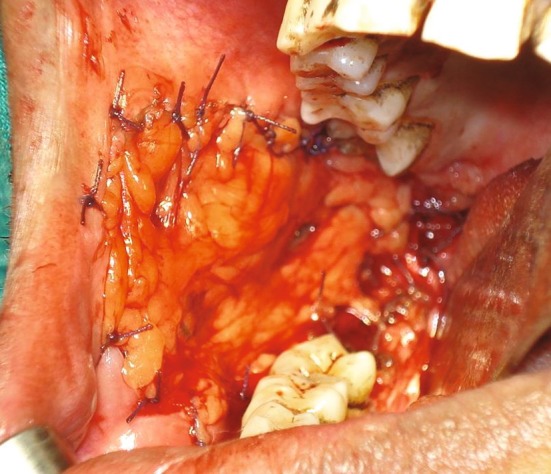

Fig. 3.

Reconstruction of the defect after surgical excision with buccal fat pad (BFP)